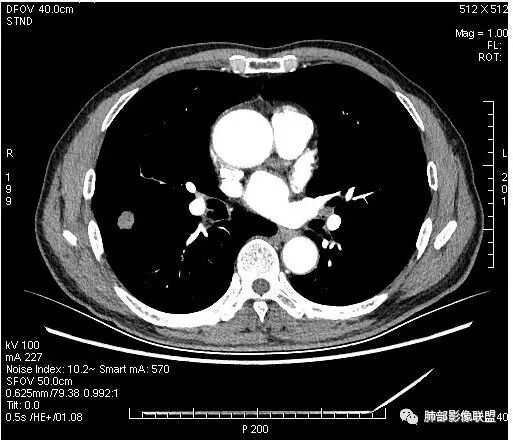

傅昌瑜:

晨读:男,67岁,体检发现右肺结节。近圆形,支气管及伴行血管进入结节,进入结节后支气管堵塞,血管走形尚自然,结节内血管边缘凹凸不平。远端边缘见毛刺(软毛刺?)及分叶。见胸膜牵拉。实变中见空洞。整体膨胀感不明显。考虑炎性肉芽肿可能,隐球菌病可能性大。注意鉴别鳞癌、结核。

虽然良恶性征象都有,但是这个病灶增强后坏死比较明显,如果是恶性:腺癌这样大小的结节坏死很少见,只有低分化腺癌可以坏死,但是低分化腺癌这种大小一般会有周围转移表现(叶间胸膜结节,癌淋或者淋巴结明显肿大),如果是鳞癌,收缩力,坏死情况以及没有支气管截断都不太支持,而且结节远端有几个小结节样改变,大家可能认为是血管,但我觉得应该是卫星灶。所以觉得隐球可能较大。壁胸膜的牵拉线也没有引起胸膜凹陷,比较纤细,至于病理中的丝状物不一定是真菌菌丝。

这个大部分边缘稍微偏平直一点,血管走行非常自然,包括里面的空泡征样的,影子很干净,边界很光滑,都是些炎性特点。